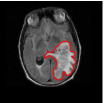

We adopt and suitably customize the shape definition of Srivastava et al. (2011) that is particularly attractive in the current context (see (Joshi et al., 2007a, b), (Srivastava et al., 2011), and (Kurtek et al., 2012) for details). While describing the tools, we concurrently illustrate their usage on the GBM dataset. To get an idea of this problem’s complexity, we display a few examples of tumor contours overlaid on the corresponding T1-weighted post-contrast and T2-weighted FLAIR MRI slices in Figure 2. The tumor shapes are heterogeneous and at first glance, it is difficult to ascertain any relationship between tumor shapes and survival times. To obtain insight into possible relationships between tumor shapes and outcomes, more sophisticated approaches are required.